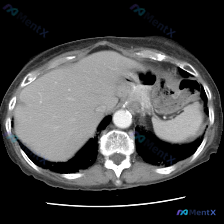

用户预设了“脾脏病变”的方向,提供了一张腹部CT横断面软组织窗图像,从分析来看是增强扫描的动脉期或早期门脉期。

✅ 图像质量:清晰度良好,无明显运动/金属伪影,软组织辨识度高

✅ 肝脏:形态自然,密度均匀,无明确占位,血管走行正常

✅ 胰腺:可见胰体尾部,实质密度均匀,胰周脂肪间隙清晰,无渗出或肿块

✅ 脾脏:形态、大小正常,实质密度均匀,未见异常结节或占位

✅ 胆囊:该层面显示不全,周边无明显积液/炎症

✅ 腹膜后:腹主动脉走行正常,周围无肿大淋巴结

✅ 其他:腹腔内无游离气体/腹水,胃壁无异常增厚,脊柱骨质完整

📌 重点:综合来看,这张单帧CT上没有发现任何明确的病理性改变,属于影像学阴性。